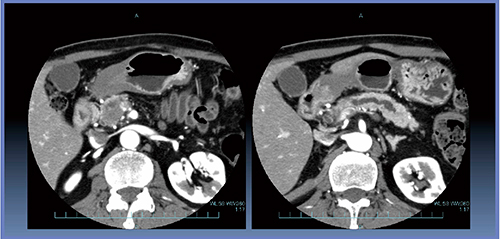

症例1は,下部胆管がんでsoft pancreasの症例である(図3)。Perfusion解析では,AF=110.4±9.3mL/min/100mL,MTT=8.8±0.7sとなっている(図4)。本症例では,術後10日目に膵液瘻による膵液貯留が認められ,CTガイド下ドレナージを施行し,Grade Bと判定された。

図3 症例1:下部胆管がん(POPF:Grade B)